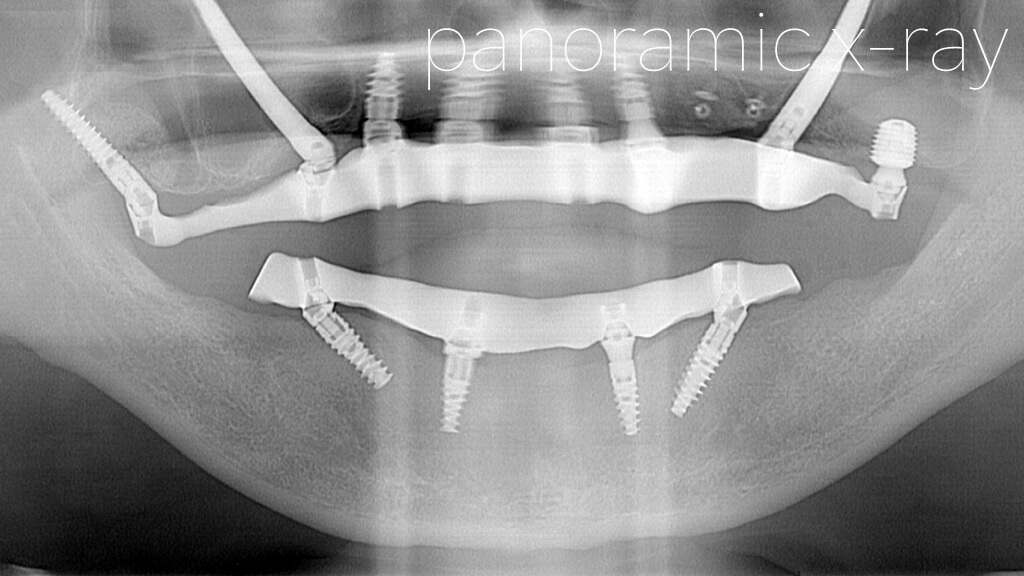

初診時のパノラマX線写真と口腔内写真です。

かなりボロボロの状態で来院されました。

インプラント手術後

計画通りに上顎はオールオン4ザイゴマインプラント、下顎はオールオン4による手術を行いました。

さらに上顎の右側にテリゴイドインプラント、左側にワイド・ショートインプラントを追加することで安定性が高まりました。

上顎右側後方に埋入したザイゴマインプラントとテリゴイドインプラント。

上顎左側後方に埋入したザイゴマインプラントとワイド・ショートインプラント。